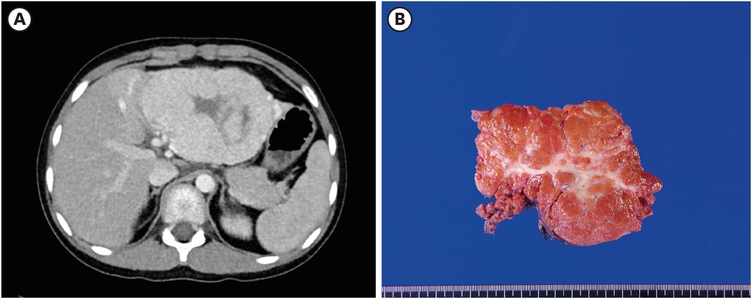

When he got surgery, he was 140 cm and 30 kg with BMI 15.7 kg/m2. American Society of Anesthesiologists physical status classification score was one. He went through robotic assisted partial hepatectomy. Tumor was located in segment II, III, IV and size was 12.0×7.0 cm. Operation time was 193 minutes. There was no complication including bleeding and he was discharged in postoperative day 6, same as 1st case patient (Fig. 2).

Fig. 2

Case 2. (A) preoperative abdominal pelvic CT scan; (B) resected specimen.

CT, computed tomography.